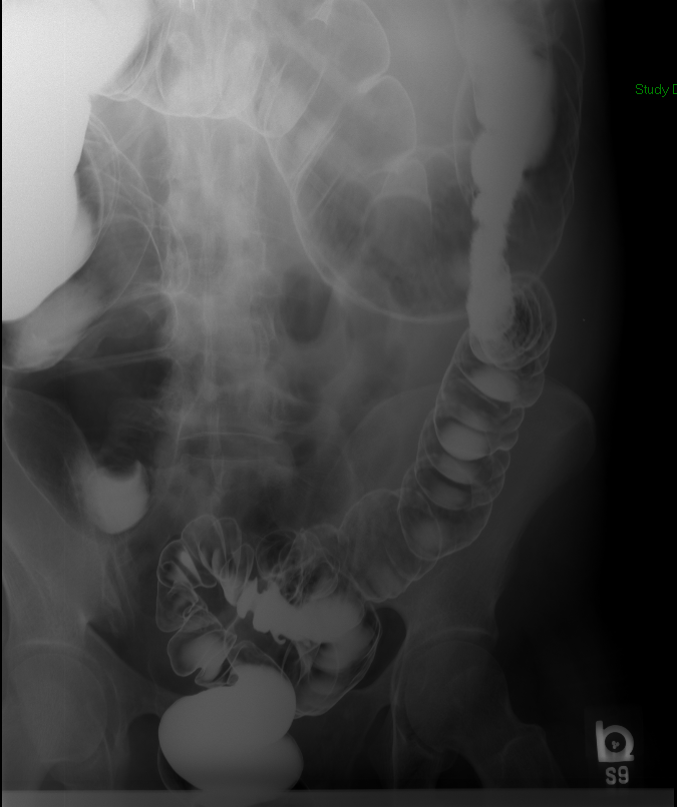

- The technologist will obtain a scout image. Assess the image for any possible contraindications such as pneumoperitoneum, evidence of ileus or obstruction, or residual contrast material

(key image 1).

- Once 15 minutes has passed since the patient drank the barium, the technologist will obtain a prone (if possible) radiograph

(key image 2).

- The technologist will obtain radiographs at 30, 45, and 60 minutes after the initial administration of barium. If the column of contrast material has not reached the large bowel on the 60 minute film, the technologist will obtain images every 30 minutes until contrast can been seen in the cecum

(key image 3)

(key image 4)

(key image 5).

- The technologist will have you review every image.

- Obtain images of the terminal ileum and the ileocecal valve filled with contrast material

(key image 6)

(key image 7)

(key image 8)

(key image 9)

(key image 10).

- Obtain spot images of the remainder of the small bowel

(key image 11)

(key image 12)

(key image 13)

(key image 14).

- Obtain images of all four quadrants. Use the compression paddle to separate loops of small bowel from each other.